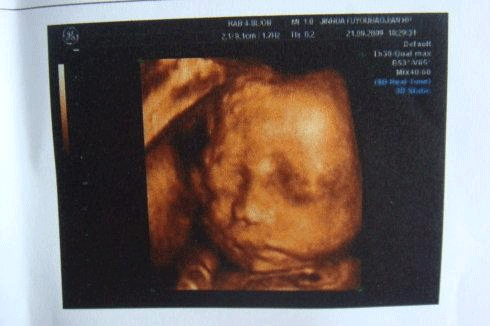

30周4天的小排畸检查

而小排畸的检查方式一般会使用高分辨力的彩色多普勒血流显像仪检查,主要是四维彩超一般黑白B超只要求进行上述常规超声检查内容,一般不用黑白B超进行详细系统胎儿畸形超声检查。

小排畸检查在30周左右

小排畸检查报告单

一般大排畸都是采用的四维彩超检查,主要观察染色体异常标记,监测胎儿在宫内的发育情况。而小排畸只需做普通B超就可以,因为此时胎儿已经到了孕晚期,通过普通B超就能看到是否存在异常。